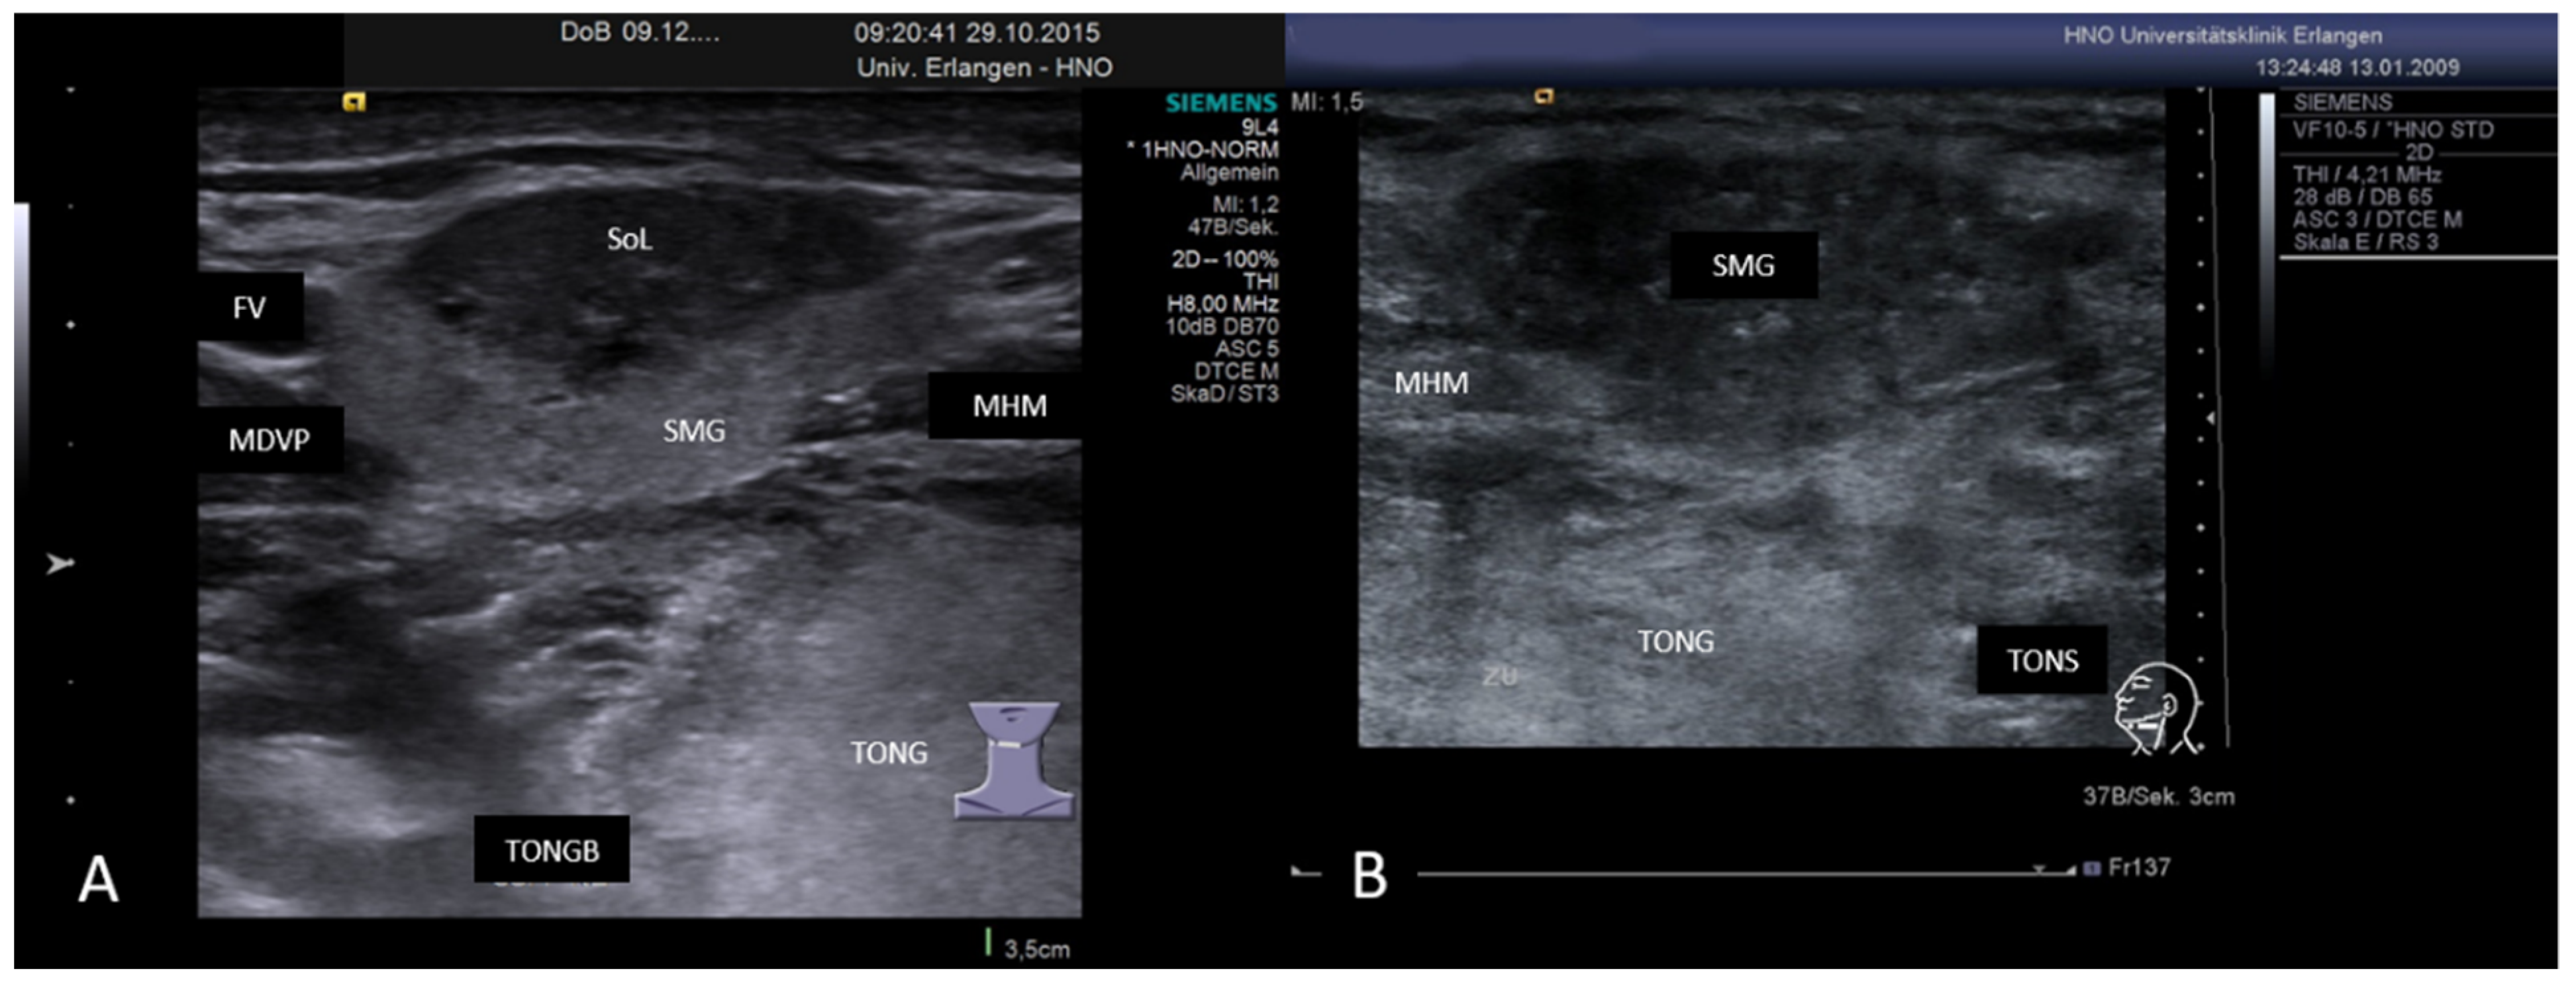

3.3.3. Non-Sialolithiasis-Caused Unspecific Sialadenitis with Sialodochitis and/or Duct Stenosis with Primary or Secondary Obstruction

3.4. Disease-Associated Inflammatory Sialadenitis with Sialodochitis (and Possible Secondary Obstruction)